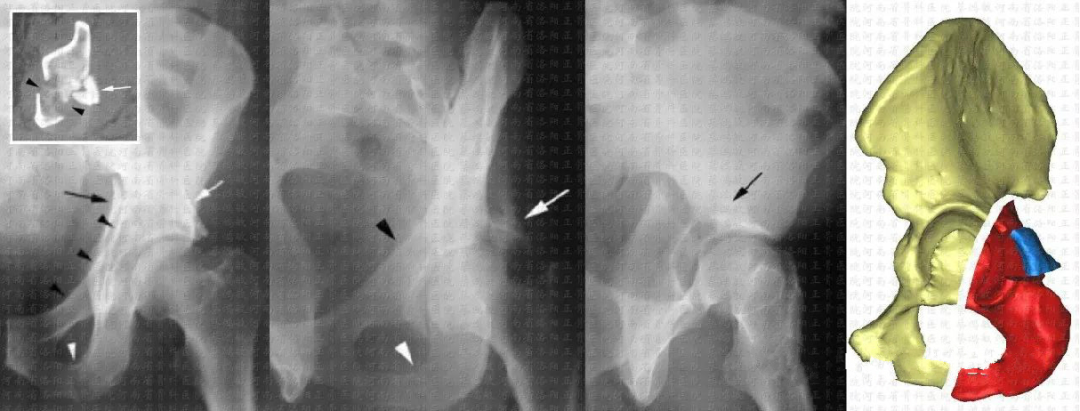

简单型     后壁骨折(25%)

简单型     后柱骨折(3%~5%)

简单型     横形骨折(5%~19%)

复杂型    后柱+后壁骨折(3%~4%)

复杂型    横形+后壁骨折(20%)

复杂型    T型骨折(7%)

复杂型    前柱/壁+后半横形骨折(7%)

复杂型    双柱骨折(23%)